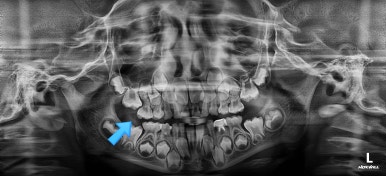

어금니 방향이 서서히 변해가는 것을 보실 수 있을 것입니다.

단 3개월만에 제대로 못나오던 어금니 위치가 바로 잡혔습니다.

왼쪽이 부산어린이치아교정 시행 전 X-ray, 오른쪽이 시행 후 X-ray 입니다.

3개월만에 많이 좋아졌습니다.

이미 앞쪽 유치의 뿌리 일부가 어금니 때문에 녹은 상태이기 때문에 수명이 짧아질 수 있다는 점. 만약에 제 시기보다 조기에 뽑힌다면 공간유지장치 등으로 뒤쪽 어금니가 다시 앞으로 쏠리지 않도록 막아줘야 된다는 점 등이 주의점이 되겠습니다.